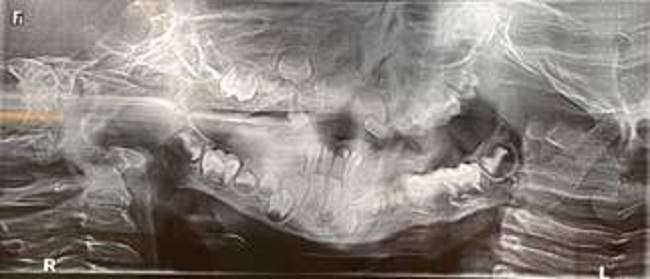

En relación al examen radiográfico, la radiografía panóramica inicial (Figura 5) mostró ausencia de muchos dientes temporarios, y también se observó presencia de gérmenes de dientes permanentes y retraso en la erupción dentaria de algunos dientes, lo que requería un acompañamiento.